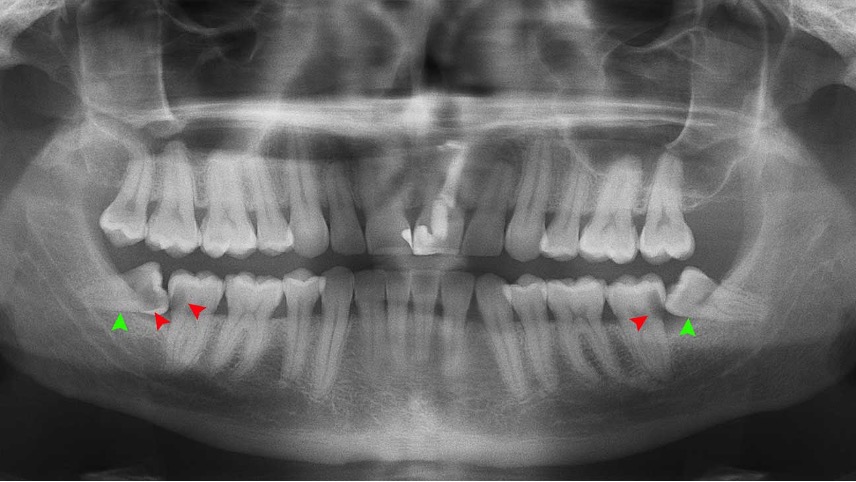

Panoramic X-ray- The Lower wisdom teeth (3rd molars) leaning forward causing a

food trap and cavities on the 2nd molars

Impacted wisdom tooth leaning forward

Flap of tissue partially covering the wisdom tooth. Circled area behind is infectedfood trap and cavities on the 2nd molars